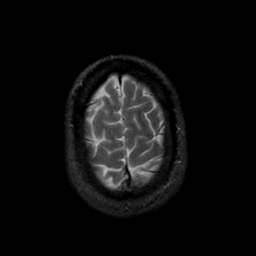

MR Study #9, April 14, 1991 -- Slice #44